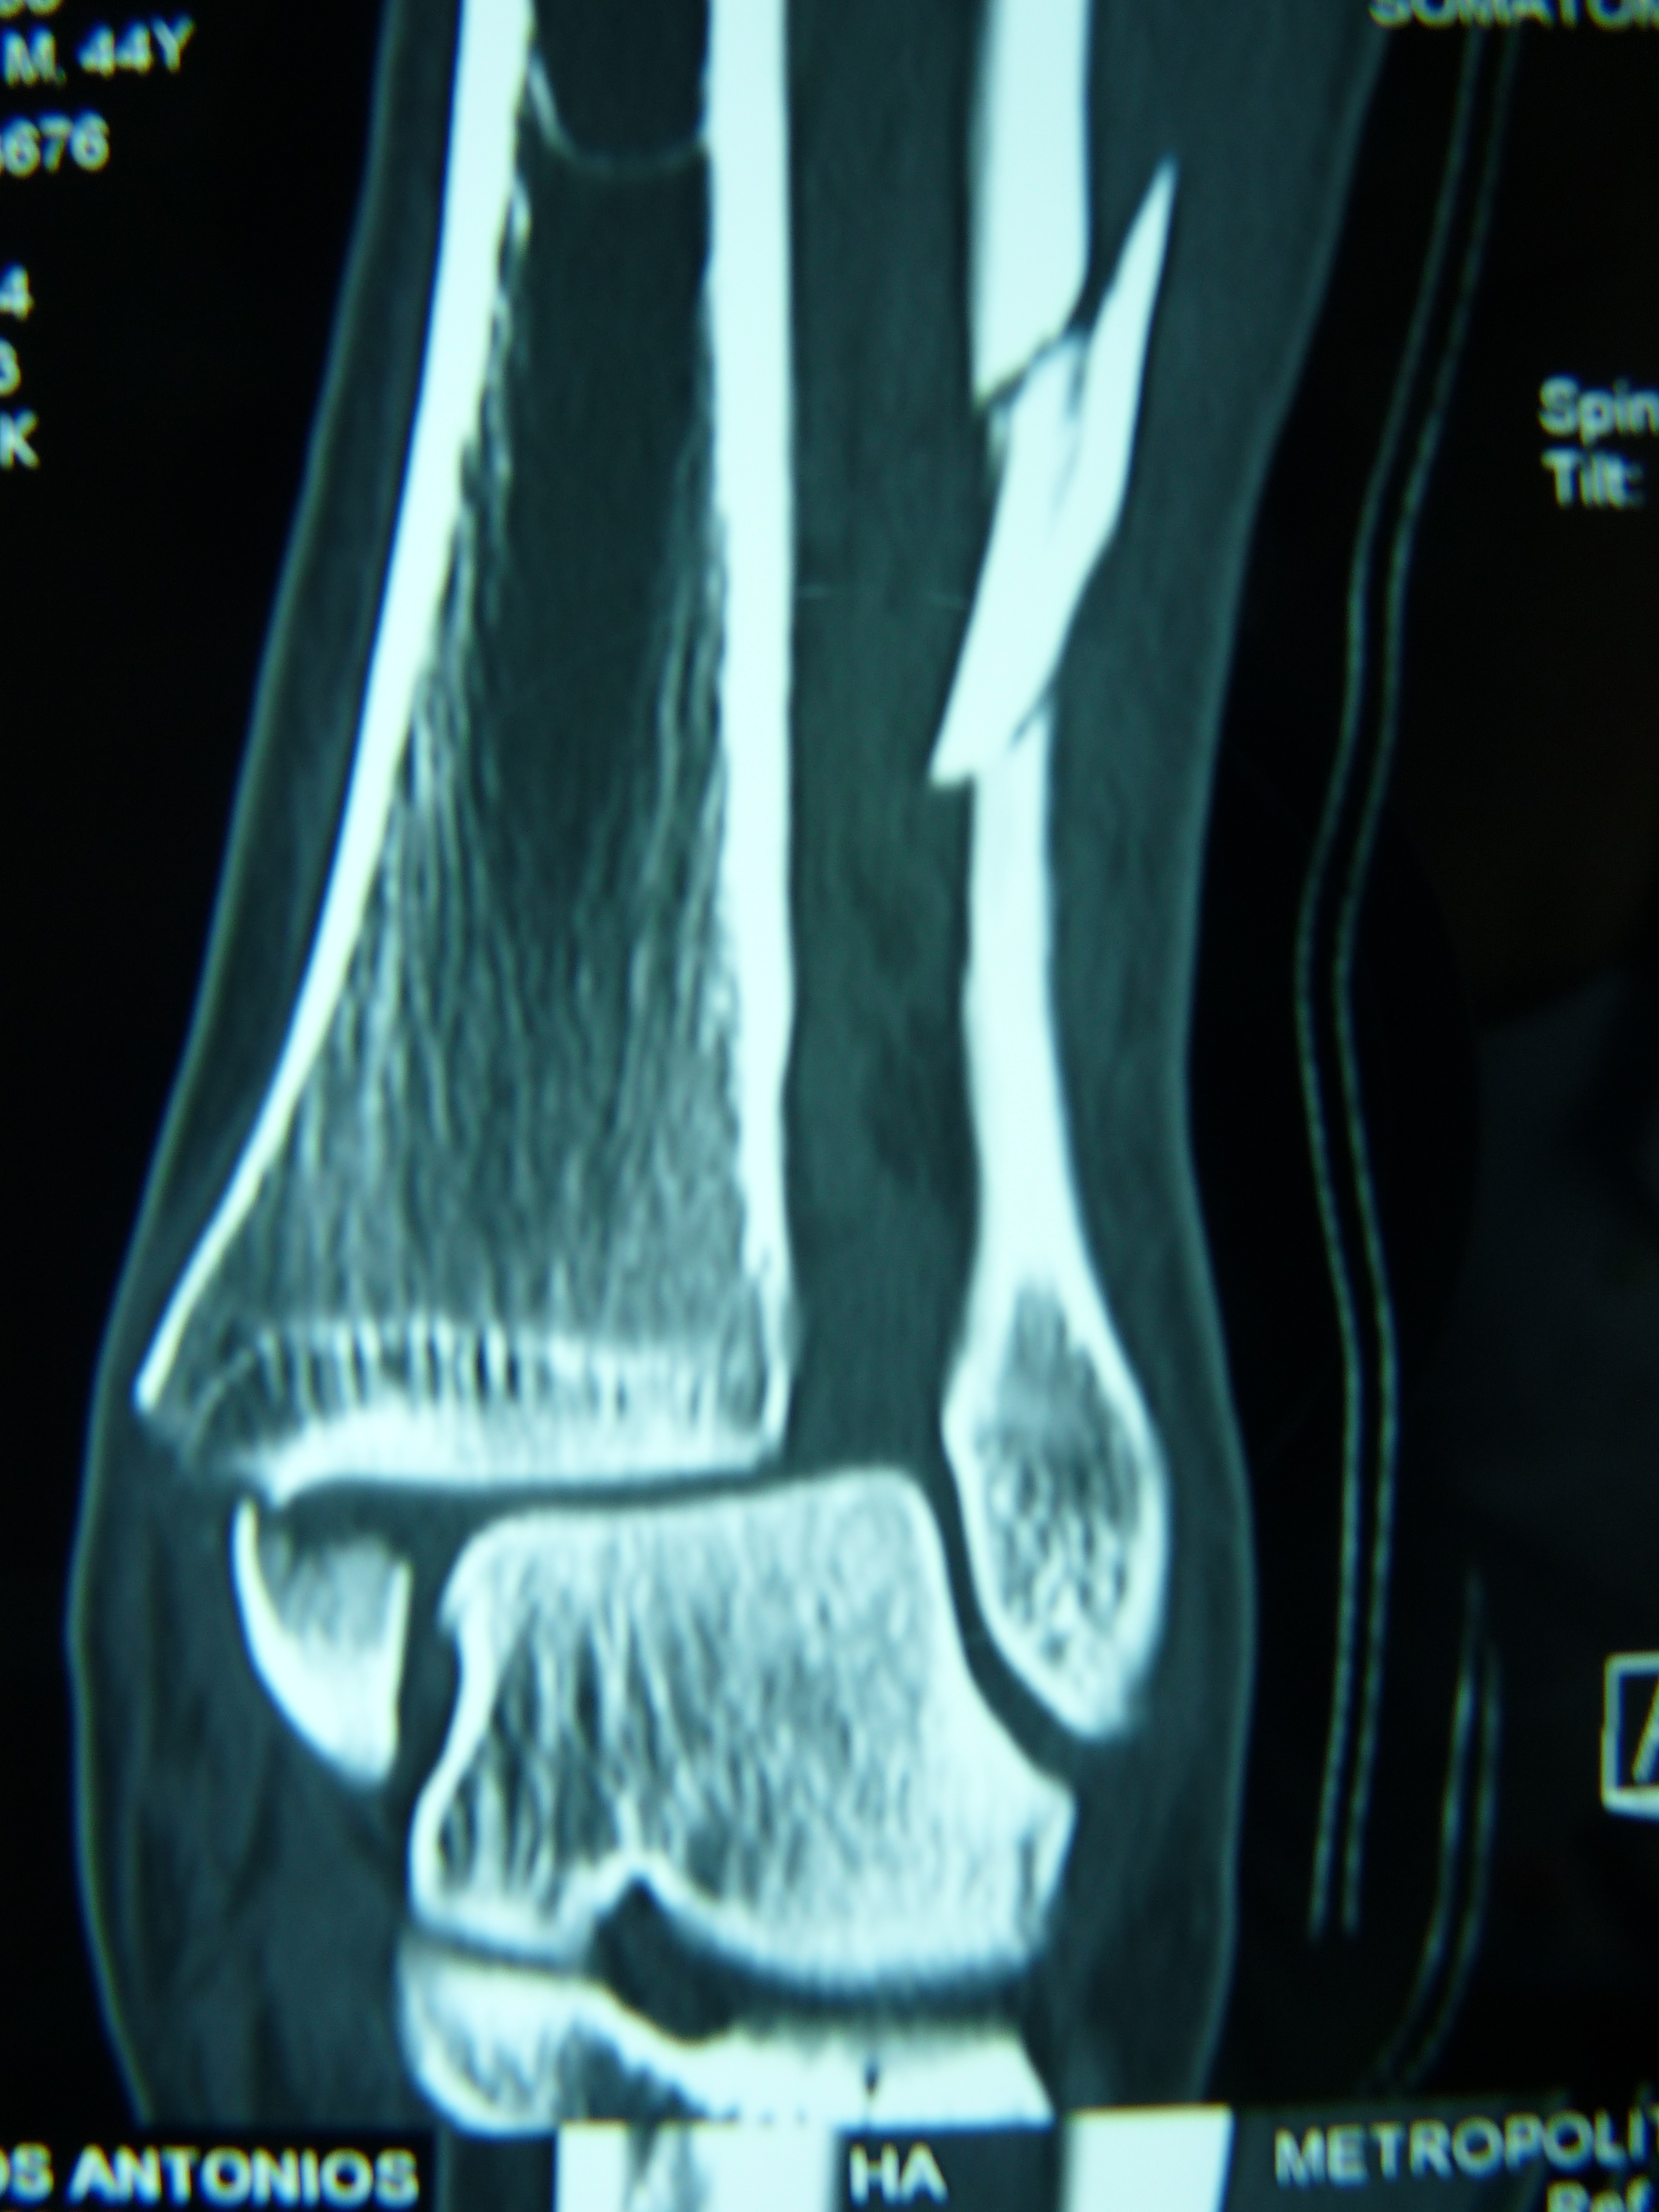

Εικόνα 3: α Προσθιοπισθία και β Πλαγία μετεγχειρητική (3 μήνες μετά) ακτινογραφία της ποδοκνημικής άρθρωσης

Παρατηρείται η σωστή θέση της ποδοκνημικής άρθρωσης και η ακεραιότητα των υλικών